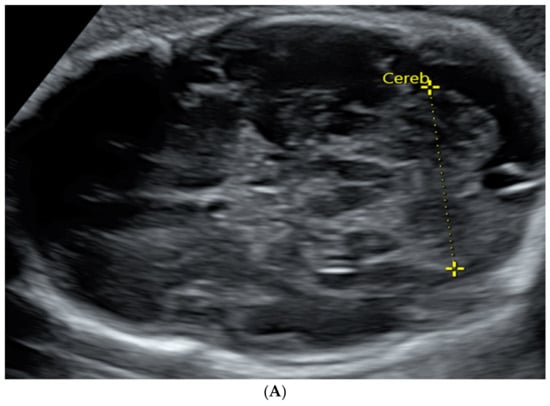

Figure 1.

TCD measured in an image by trans-abdominal axial US scan at 31 weeks of gestation (A) and by coronal MRI scan at 32 weeks of gestation (B).